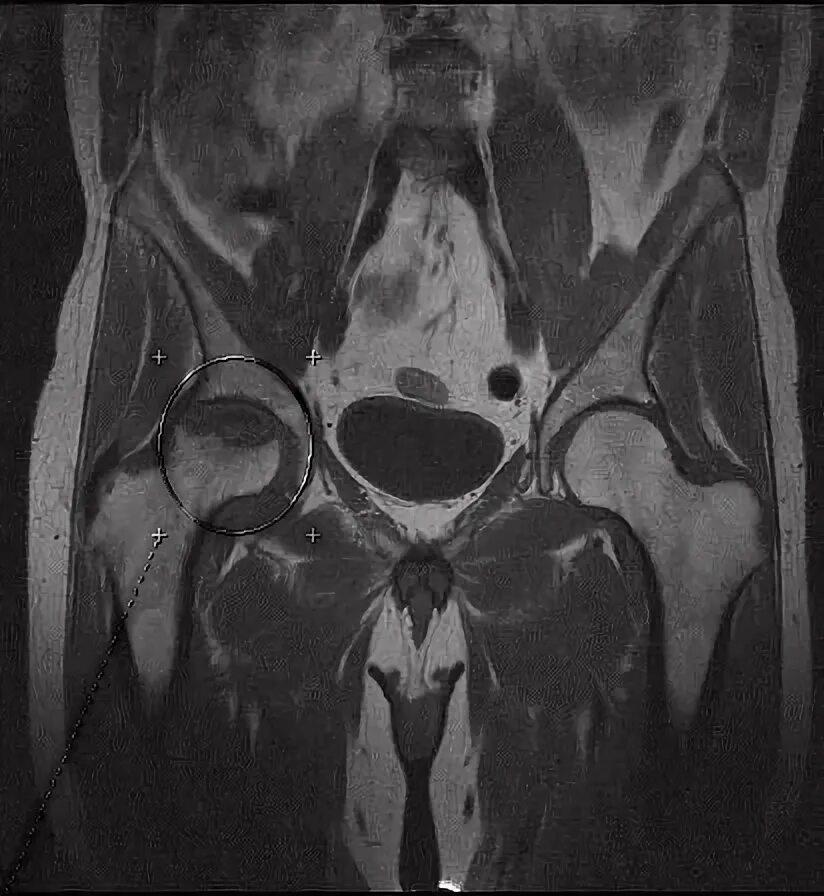

Мрт тазобедренного сустава в минске